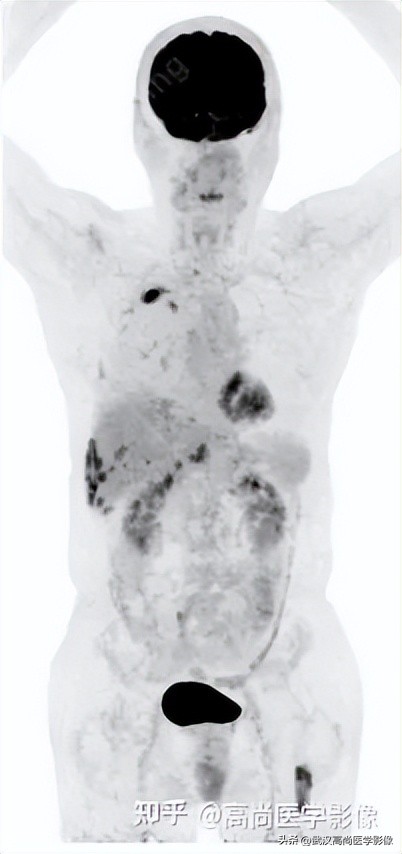

PET/CT寻找原发灶

PET/CT表现:

全身(右侧颈部、双侧锁骨上区、双侧腋窝、右侧胸小肌后间隙、右侧肺门、纵隔、胰腺周围)多发淋巴结肿大,最大约3.8cm×3.3cm,FDG高摄取,SUVmax6.6。

脾脏一低密度结节,FDG高摄取,SUVmax为3.6。

左侧第2、7肋骨质破坏,合并病理性骨折。

右肺上叶后段一实性结节,大小约1.4cm×1.0cm×1.2cm,边缘分叶征、棘状突起,邻近胸膜稍牵拉,FDG高摄取,SUVmax6.6。

高危结节

PET/CT诊断结论

右肺上叶后段周围型肺癌,伴淋巴结、脑、脾脏、肋骨多发转移。